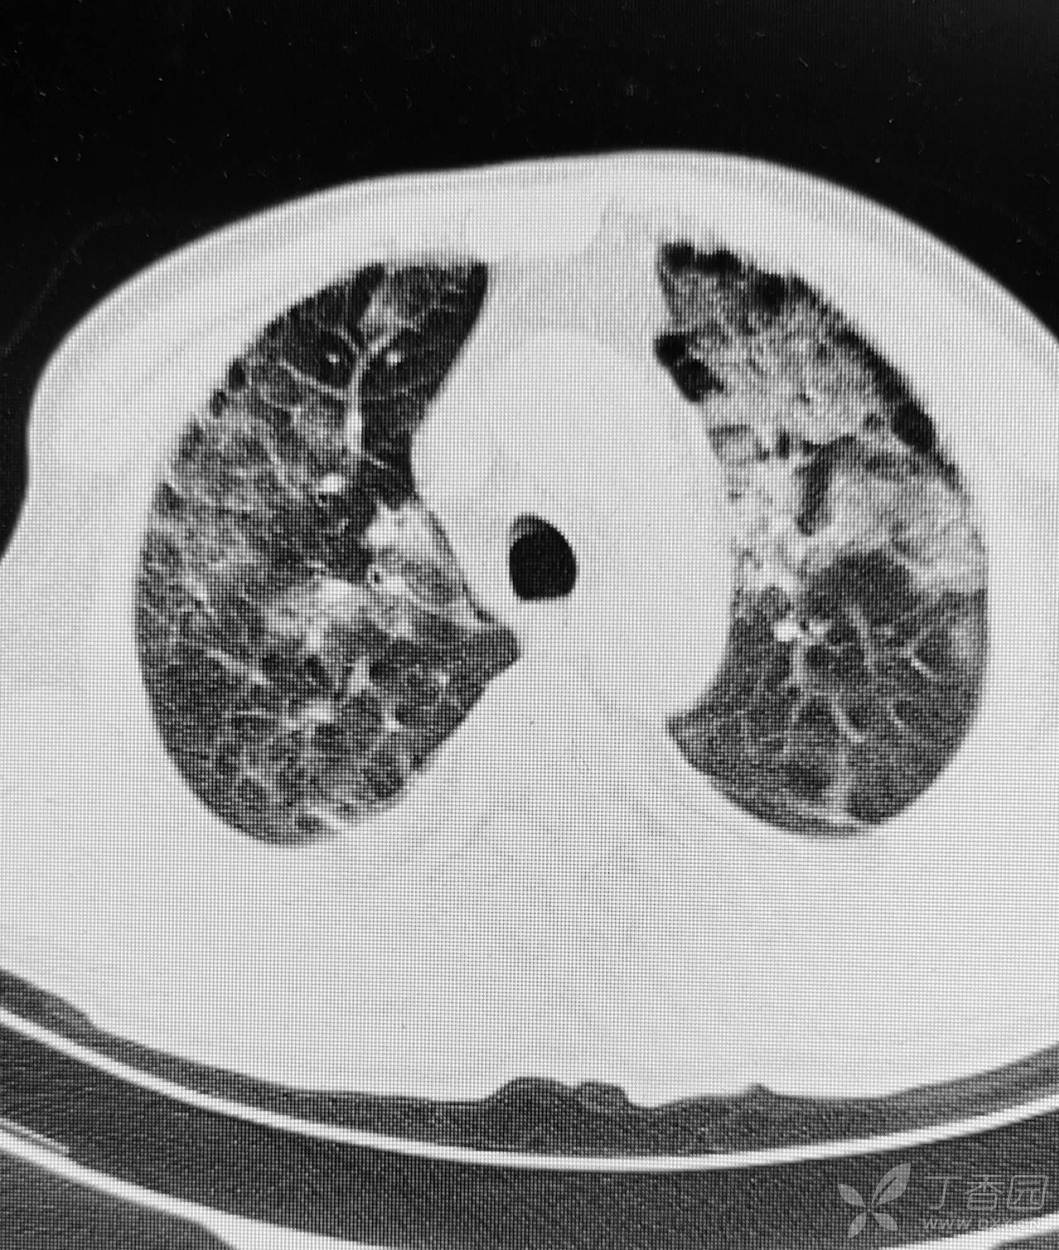

直肠癌术后两个月,接受放化疗一个月。白细胞危急值。

停化疗放疗,升白药物。白细胞增高了。

血小板仍低,血红蛋白开始降低。

胸部影像如图。

目前有血培养阳性,病原菌难以命中。痰培养阳性。